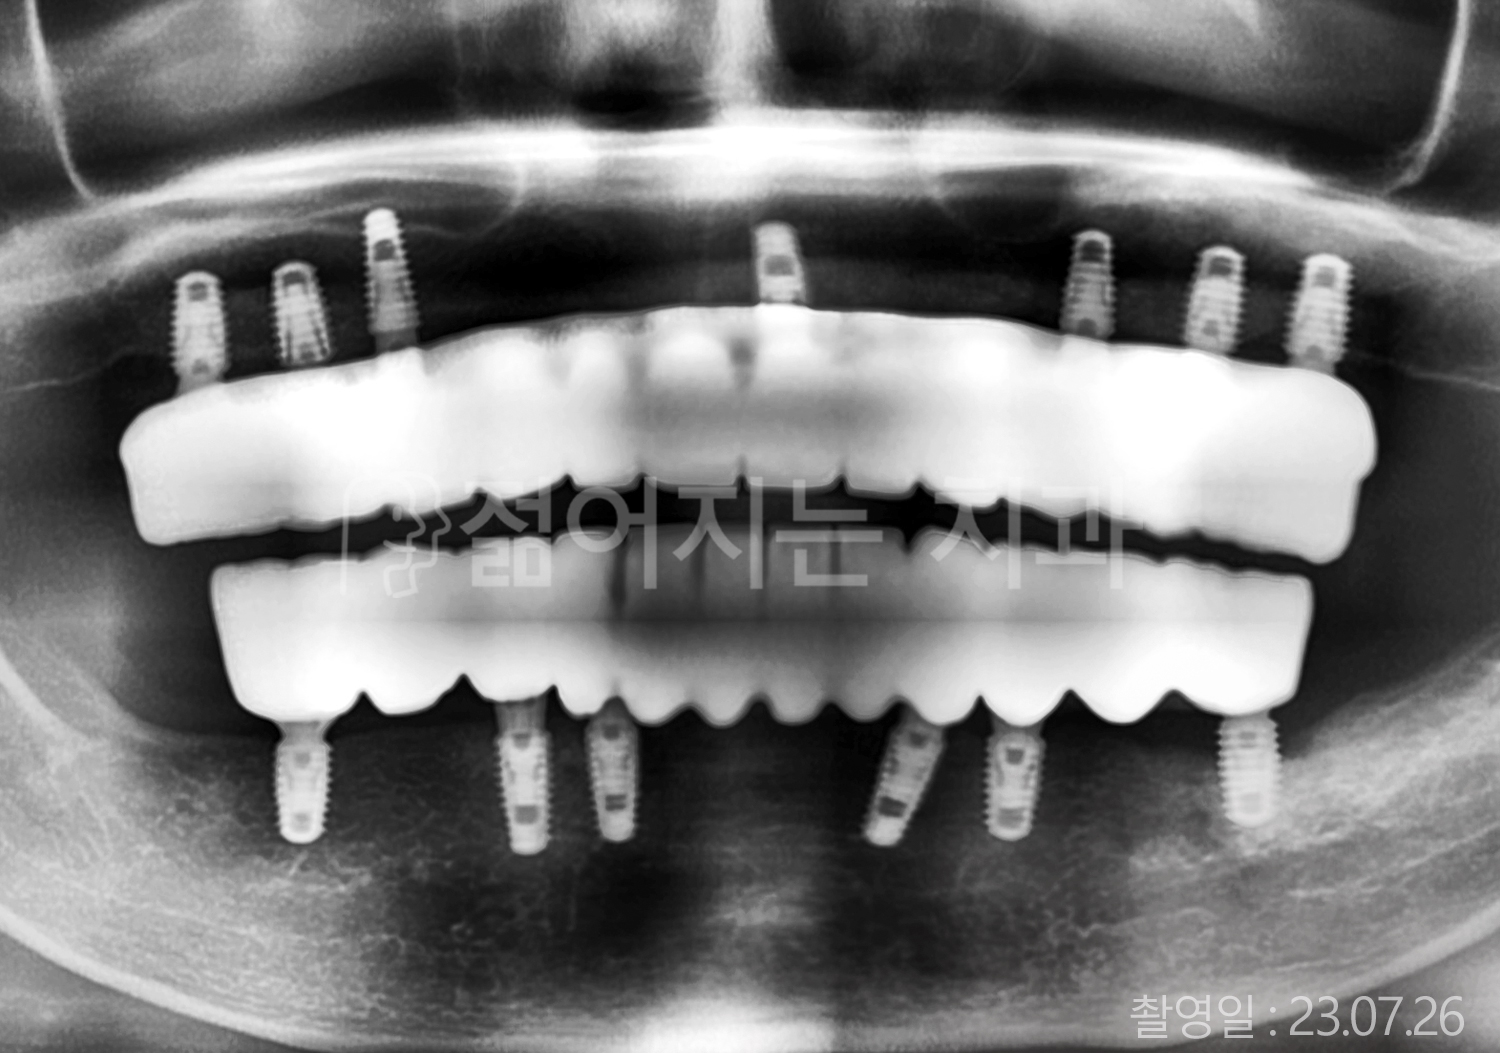

치료부위

식립개수

특이사항